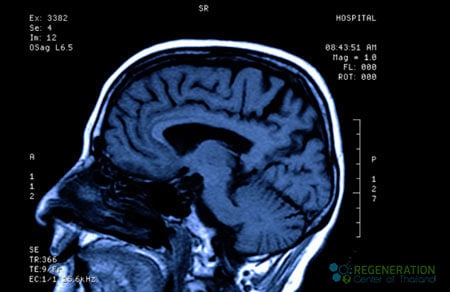

The GCS scale can also be changed after the victim is resuscitated, post-traumatic amnesia (PTA), or after recovering from the loss of consciousness (LOC). Other methods of classifying the severity of TBI include using neuroimaging scans from CT, MRI, or PET to measure brain swelling, diffuse injury, or focal lesions. A mild TBI is also commonly known as a concussion, but such an injury result in brain contusion or lead to trauma-induced paralysis.

Our treatments protocol for Traumatic Brain Injuries will require a minimum of 14-21 nights in Bangkok. Due to the significant differences in brain injury treatment requests, our medical team will need to qualify the potential candidate for treatment. Upon acceptance, a detailed treatment plan will be provided and include the specifics of the treatment plan that will include: total number nights required along with the total medical related expenses including cell extraction, enrichment, and infusions (excluding accommodations or flights). To begin the qualification process for multi-stage TBI neural stem cell transplants, please prepare your recent medical records such as recent Brain MRI’s, CT Scan (Preferred) or PET Scans and contact us today.